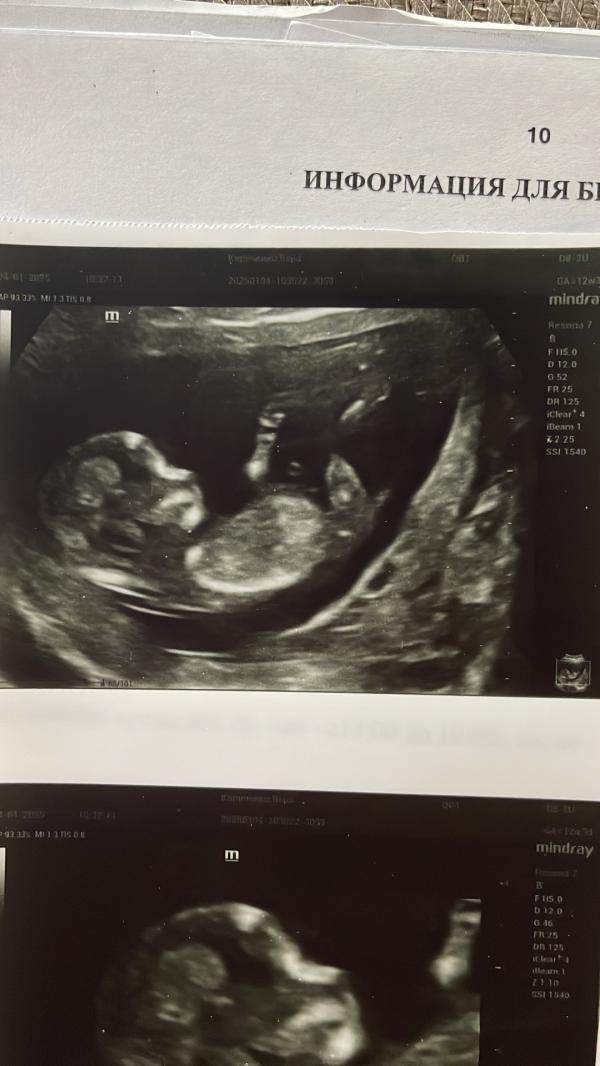

Делала скрининг в 13,6. Можно сделать на 16 неделе еще один скрининг, тройной/или четверной тест и добавить еще один показатель.

Была похожая ситуация, Середавина задерживали результаты 1 скрининга, сдавала анализ Prisca 2. Я сдавала в инвитро, но он много где есть думаю. Там высчитывается риск трисомии 21, трисомии 18 и дефекта нервной трубки. То есть нет риска трисомии 13 как в классическом анализе Astraia, вместо него дефект трубки считают. Также нет рассчета PAPP, только b-хгч. И нет рисков преэклампсии, преждевременных родов и задержки роста плода. Это лучше, чем ничего, конечно, но мне и в итоге отдали результаты 1 скрининга

Если есть возможность, сдайте нипт, если нет, можете начать с prisca 2, она намного дешевле🙏

Знаю, что некоторые девочки, которым тоже не сделали кровь скрининг из-за проблем с реактивами, сдавали нипт

В любом случае нипт остаётся сдавать